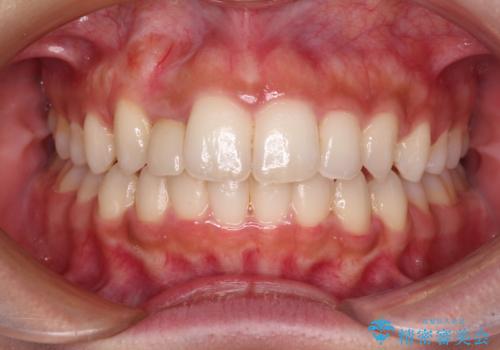

- 上下前歯のデコボコを気にして来院された患者様です。

前歯のセラミックが装着されている歯は、歯根が短くなっており、他院では抜けてしまうので矯正はできないと言われていたようです。

患者様と相談し、抜けてしまった場合にはインプラントあるいはブリッジによる補綴治療が必要となることを確認し、極力歯根に負担のかからないような仕上がりで治療を進めて行くこととしました。

デコボコを解消には、IPR(歯と歯の間を削る)をメインに歯列排列を設計し、インビザラインにて矯正治療を行うこととしました。

レントゲン写真上では、矯正治療前後で歯根長さに大きな違いはなく、抜歯を回避することができました。

上顎内側に転位している前から2番目の歯は移動が難しく、無理矢理歯根全体を動かそうと設計すると、歯肉退縮・歯髄壊死・歯根吸収といった危険性が増すため、無難なゴールにて治療を終えることとなりました。